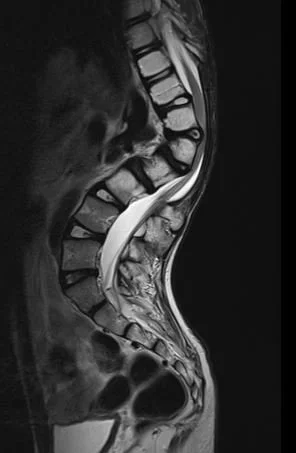

Rare and pediatric disease trials come with complex challenges that require specific expertise and experience. We have the radiology exerts to support the specific requirements of pediatric clinical trials. Many rare diseases affect children, and pediatric trials bring additional challenges.

They require specific protocols, involve additional regulations and demand expertise and experience. BICL’s experts are experienced in oncology, MSK and other pediatric disorders including growth plate disturbance, bone age and osteochondroma.